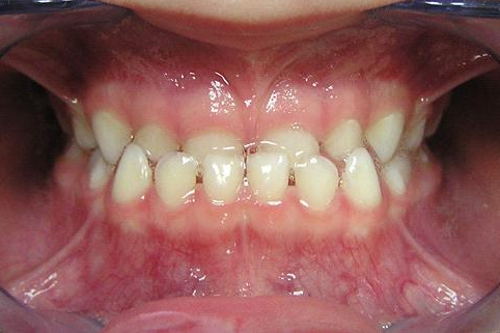

Прикусы, когда нужна ранняя коррекция, это — открытый прикус, перекрестный и обратный (мезиальный) прикус.